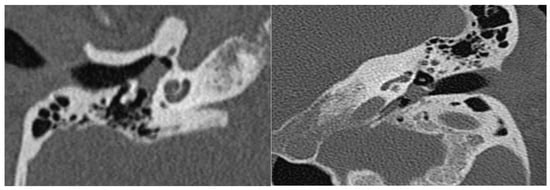

Abstract

3.3. Classification and Surgical Management

4.2. Classification and Algorithm of Surgical Treatment

| A | Tumors limited to the middle ear cleft |

| B | Tumors limited to tympanomastoid compartment of the temporal bone |

| A | Tumors limited entirely to the middle ear cleft |

| A1 | Tumors completely visible on otoscopic examination |

| A2 | Tumor margins are not visible on otoscopy. Tumor may extend anteriorly to the Eustachian tube and/or to the posterior mesotympanum |

| B | Tumors limited to the tympanomastoid compartment of the temporal bone |

| B1 | Tumor filling the middle ear cleft with extension into the hypotympanum and tympanic sinus |

| B2 | Tumor filling the middle ear cleft, extending into the mastoid and medially to the mastoid segment of the facial nerve |

| B3 | Tumor filling the middle ear cleft, extending into the mastoid with erosion of carotid canal |